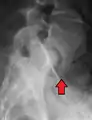

A hangman's fracture is a specific type of spondylolisthesis where the second cervical vertebra (C2) is displaced anteriorly relative to the C3 vertebra due to fractures of the C2 vertebra's pedicles.

Retrolisthesis

A retrolisthesis is a posterior displacement of one vertebral body with respect to the subjacent vertebra to a degree less than a luxation (dislocation). Retrolistheses are most easily diagnosed on lateral x-ray views of the spine. Views, where care has been taken to expose for a true lateral view without any rotation, offer the best diagnostic quality.

Retrolistheses are found most prominently in the cervical and lumbar region, but can also be seen in the thoracic area.